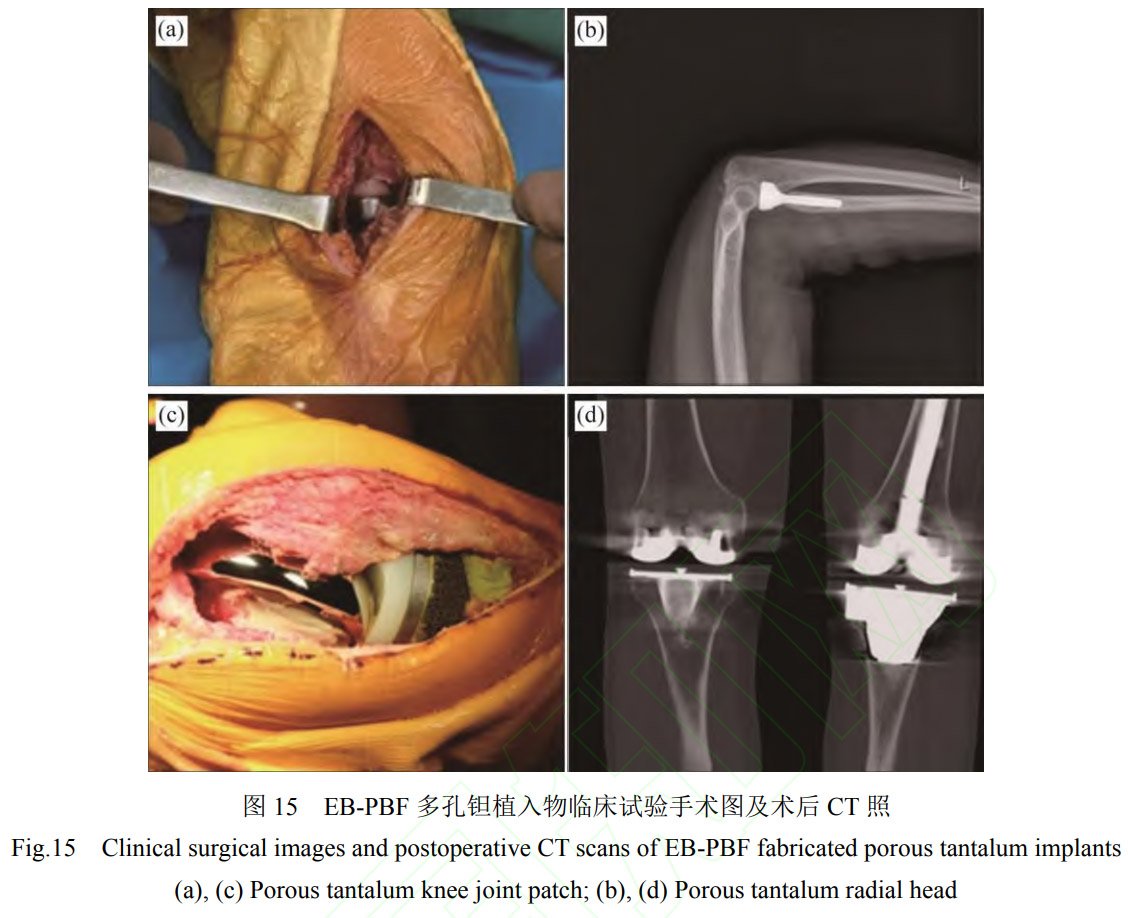

在临床试验方面,西安赛隆增材技术股份有限公司依托科技部国家重点研发计划项目“个性化多孔钽植入假体粉床电子束增材制造关键技术和临床应用”项目(2016YFB101400),累计完成100余例个性化多孔钽临床试验,患者年龄3~83岁,植入物包括多孔钽髋关节补块、膝关节补块、桡骨假体、舟骨假体等。如ZHANG等[63]利用EB-PBF多孔钽桡骨假体对7例桡骨头粉碎性骨折患者进行了桡骨头置换术,术后随访数据显示,患者术后疼痛减轻,肘关节功能改善,多孔钽假体展现出优异骨长入特性。AO等[64]观察了6例使用EB-PBF多孔钽膝关节补块进行全膝关节置换术翻修患者的恢复情况,其临床手术照片如图15所示,在术后26.3个月后,没有患者出现任何手术相关并发症,植入关节内的多孔钽假体稳定,骨缺损得到有效重建,患者膝关节功能得到明显改善。